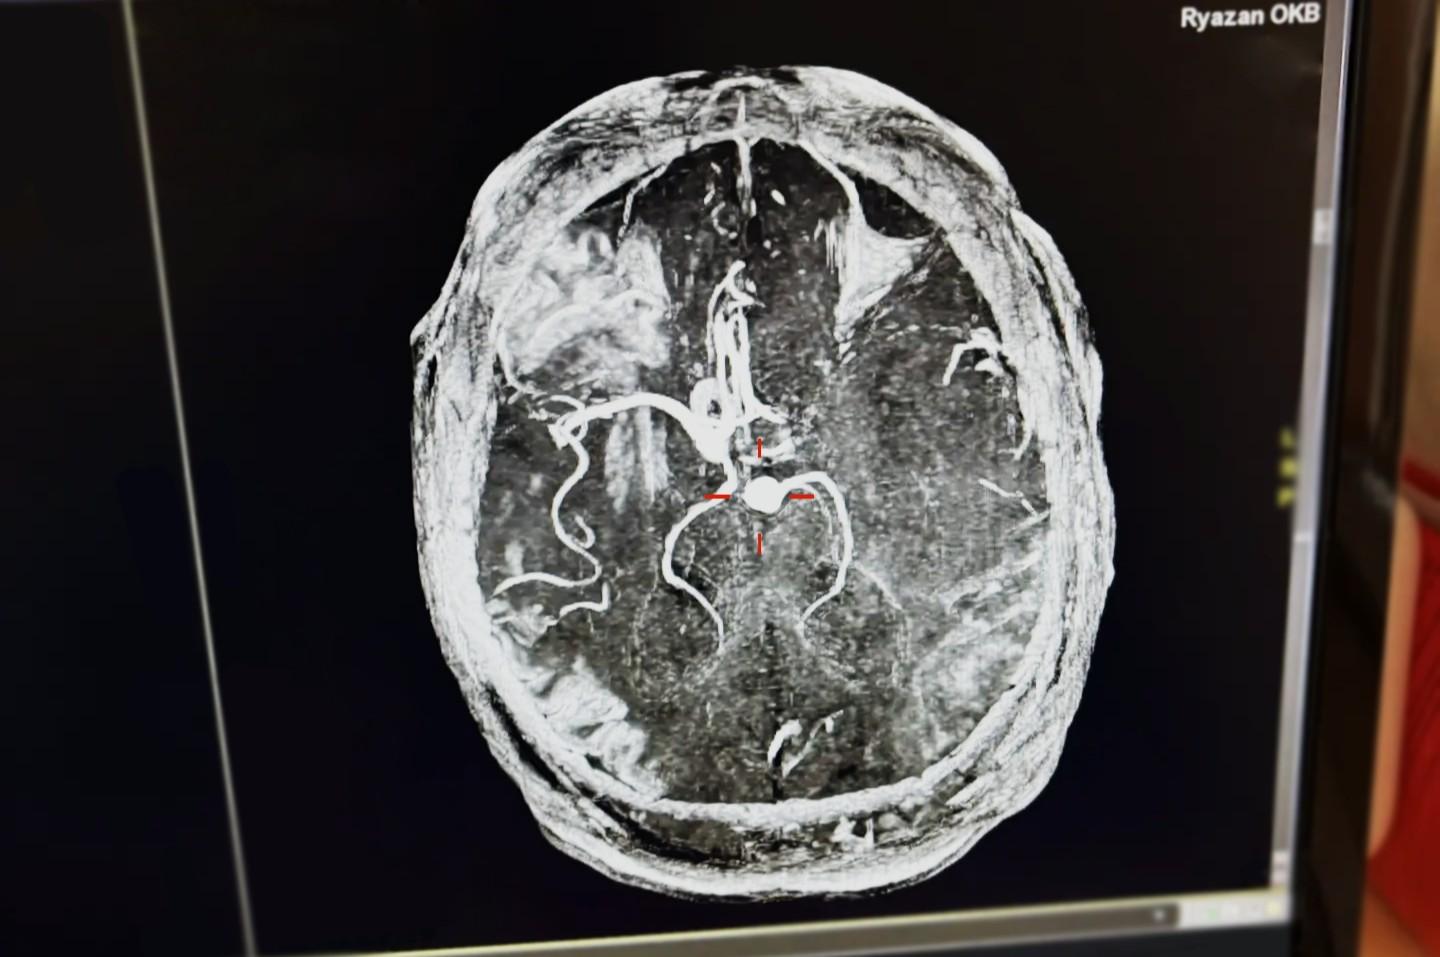

Снимок МРТ головного мозга пациента

Специалисты ОКБ провели тромболитическую терапию, введя пациенту препарат для растворения сгустка крови. Это позволило восстановить кровоснабжение в заблокированном сосуде головного мозга.